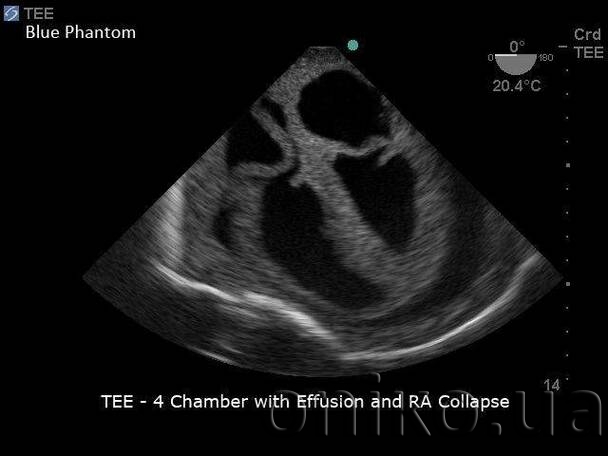

Відмінно підходить для підготовки медичних спеціалістів у техніках, пов’язаних з трансторакальною ехокардіографією (TTE), черезстравохідною ехокардіографію (ТЕЕ) та процедурним тренінгом з перикардіоцентезу, керованого ультразвуком. Навчальна платформа серцевого ультразвуку TTE / TEE дозволяє користувачам розвивати навички ультразвукової візуалізації, такі як TEE, TTE та ультразвуковий перикардіоцентез.

Ці навички включають: використання ультразвукової системи управління, введення та розміщення датчика, позиціонування та переміщення зонда, застосування належного тиску датчика для отримання зображень, розпізнавання серцевих структур, артефактів легень і ребр, інших анатомічних структур, спрямування голки та катетера до перикардіального простору для тренування перикардіоцентезу.